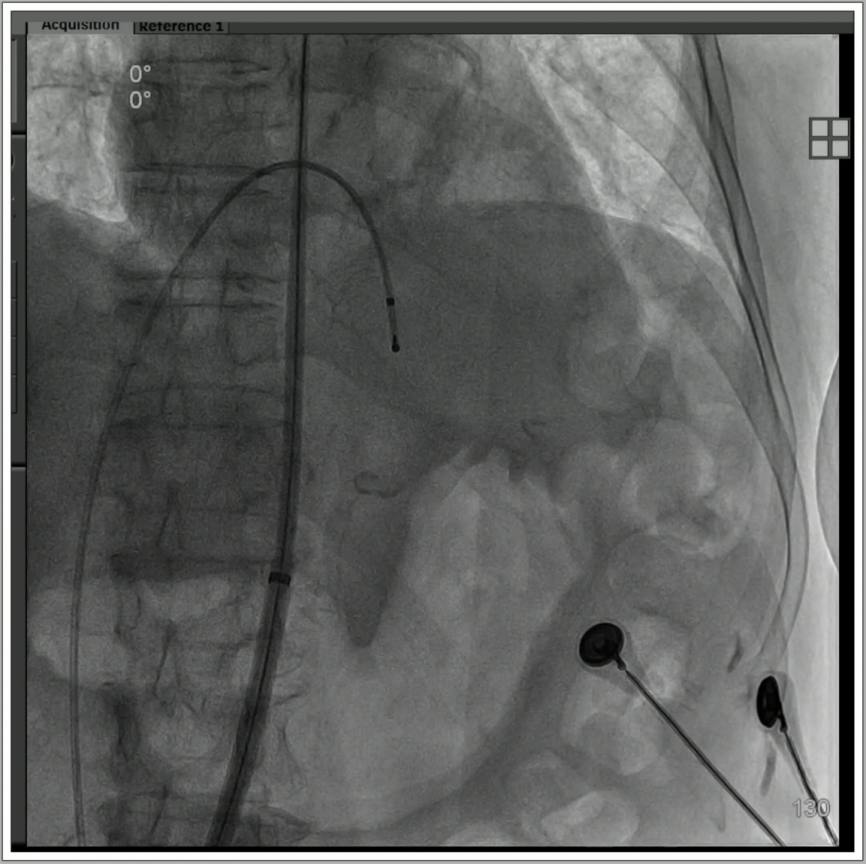

1、全麻下建立双侧股动脉入路,以右股动脉为主;血管穿刺后置入14F eSheath血管鞘。

2、导丝跨瓣后置换猪尾导管,测量主动脉瓣压差40mmHg;